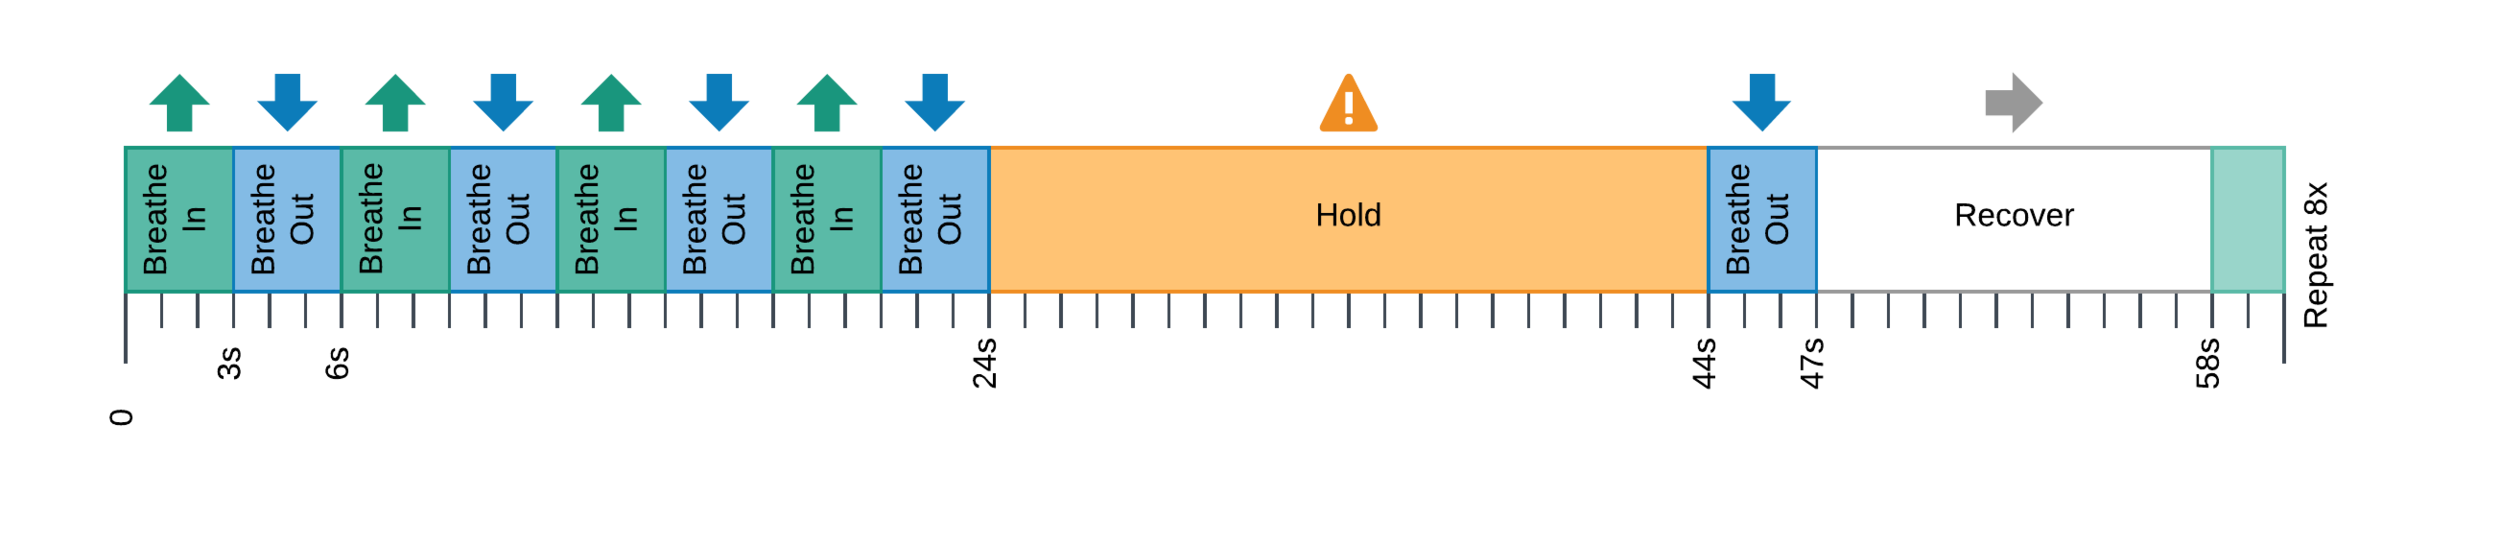

CVR can be measured during BOLD fMRI experiments with Breath-holds (BH), that induce the subject into a state of hypercapnia²

EuskalIBUR

* TR = 1.5 s, TEs = 10.6/28.69/46.78/64.87/82.96 ms, MB acceleration factor = 4, GRAPPA = 2, voxel size = 2.4x2.4x3 mm³

10 neurotypical subjects

(5F, age 25-40y)

10 sessions, one week apart, same time of the day

BH paradigm: ME-fMRI (Gradient Echo EPI)

+ SBREF image

T2w, MP2RAGE (T1w), 4 RS,

3 tasks, and BH paradigm

Methods: preprocessing

Functional:

- motion realignment

- skullstripping

- optimal combination (OC)

- distortion correction

CO2 traces:

- (supervised) peak detection

- linear interpolation of peaks and convolution with HRF

- cross-correlation with average GM signal

- creation of lagged regression (range: ±9 s, step: 0.3 s)

- interpolation to fMRI TR